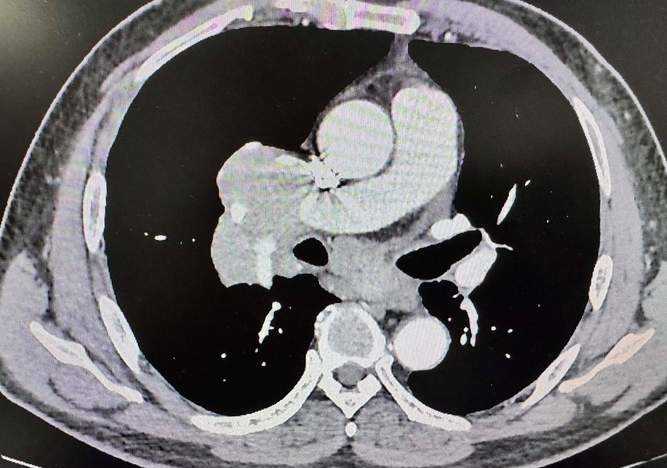

早期发现与诊断至关重要。纵隔淋巴瘤常在中年人群中显现,其初期症状与其他纵隔疾病相似,如气短、胸闷和咳嗽等。我们需要运用诸如胸部X线检查、CT检查、PET-CT以及淋巴结活检等手段,尽早明确病情。